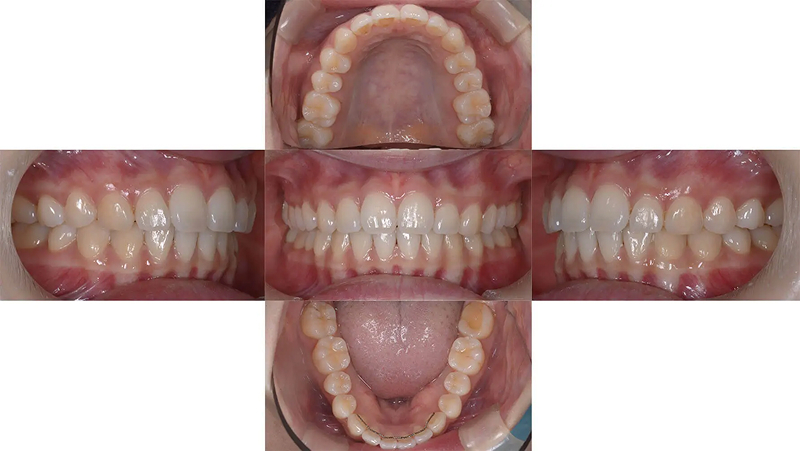

Case03左下の奥歯がとてもしみるを改善した症例

左下第1大臼歯の歯髄炎を主訴に来院されました。第2大臼歯が倒れこんでいるため、治療はできるが、歯質を多量に削合する必要があり、また、今後もむし歯リスクが高い状態が継続します。この環境から脱出するために歯列矯正を提案しました。倒れこんでいた下顎第2大臼歯は左右ともに整直し、過蓋咬合も改善しました。

初診 2017.8.1

矯正開始 2017.10.18

ファイナル 2019.8.12

| 主訴 | 左下の奥歯がとてもしみる |

|---|---|

| 診断 | 両側アングル1級の叢生を伴う過蓋咬合 |

| 矯正方法 | 矯正用アンカーを用いたマルチブラケット |

| 矯正期間 | 24か月・26回 |

| 費用 | 730,000円(税別) |

| 調整料 | 月1回 5,000円(税別) |